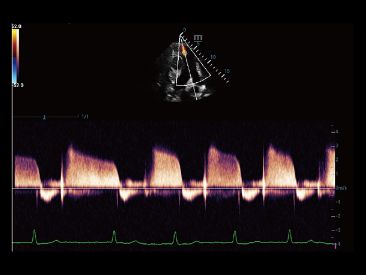

Selain kualitas gambar premium, Resona 7 juga meningkatkan kemampuan penelitian klinis dengan V Flow revolusioner untuk evaluasi hemodinamika vaskular, serta pengambilan penampang tercanggih dari rangkaian data 3D untuk diagnosis CNS pada janin. Kombinasi pengoperasian multisentuh berbasis gerakan yang paling intuitif dengan semua fitur klinis penting membuat Resona 7 menjadi gebrakan baru dalam inovasi ultrasound.